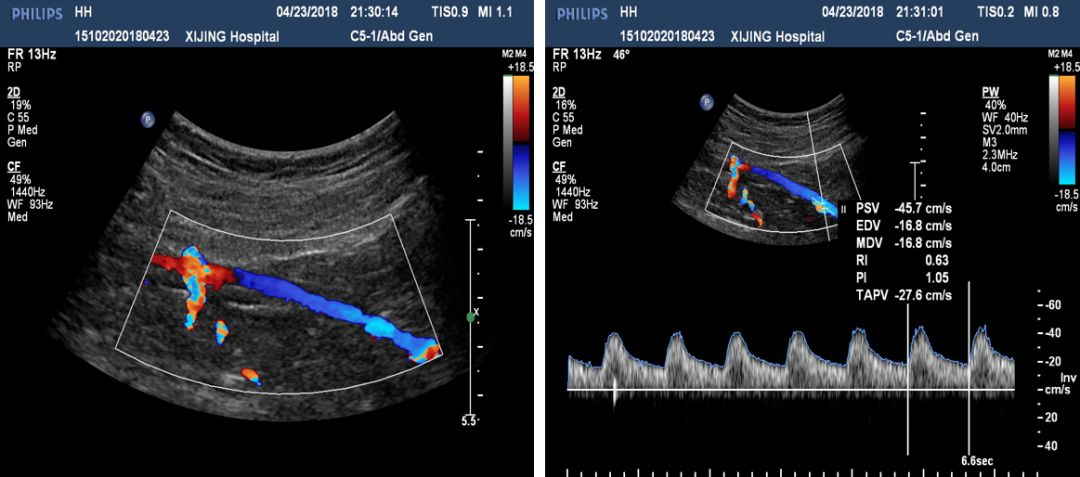

现病史:双下肢间歇性跛行4月,右足静息痛2周,跛行距离不足50米,夜间静息痛明显

既往史:既往有高血压及冠心病病史,吸烟30年,20支/天,未戒烟,合并轻度肾功能异常

查体:右小腿以远皮温减低,以右足为著;右侧股、腘、足背及胫后动脉未触及;左侧股动脉搏动尚可,腘、胫后动脉搏动未触及;左侧足背动脉搏动弱,尚可触及;ABI:(右侧)0.32,(左侧)0.79

术前检查:右髂动脉血栓

图:术前CT

图:术前超声

手术操作:系统溶栓治疗3天,症状未缓解,考虑其血栓时间较长,超声引导下行右髂动脉覆膜支架置入术

图:超声引导髂动脉覆膜支架置入术

图:髂动脉支架置入术后

图:二期开通右侧股浅动脉

手术结果:静息痛消失,正常步速行走约3千米